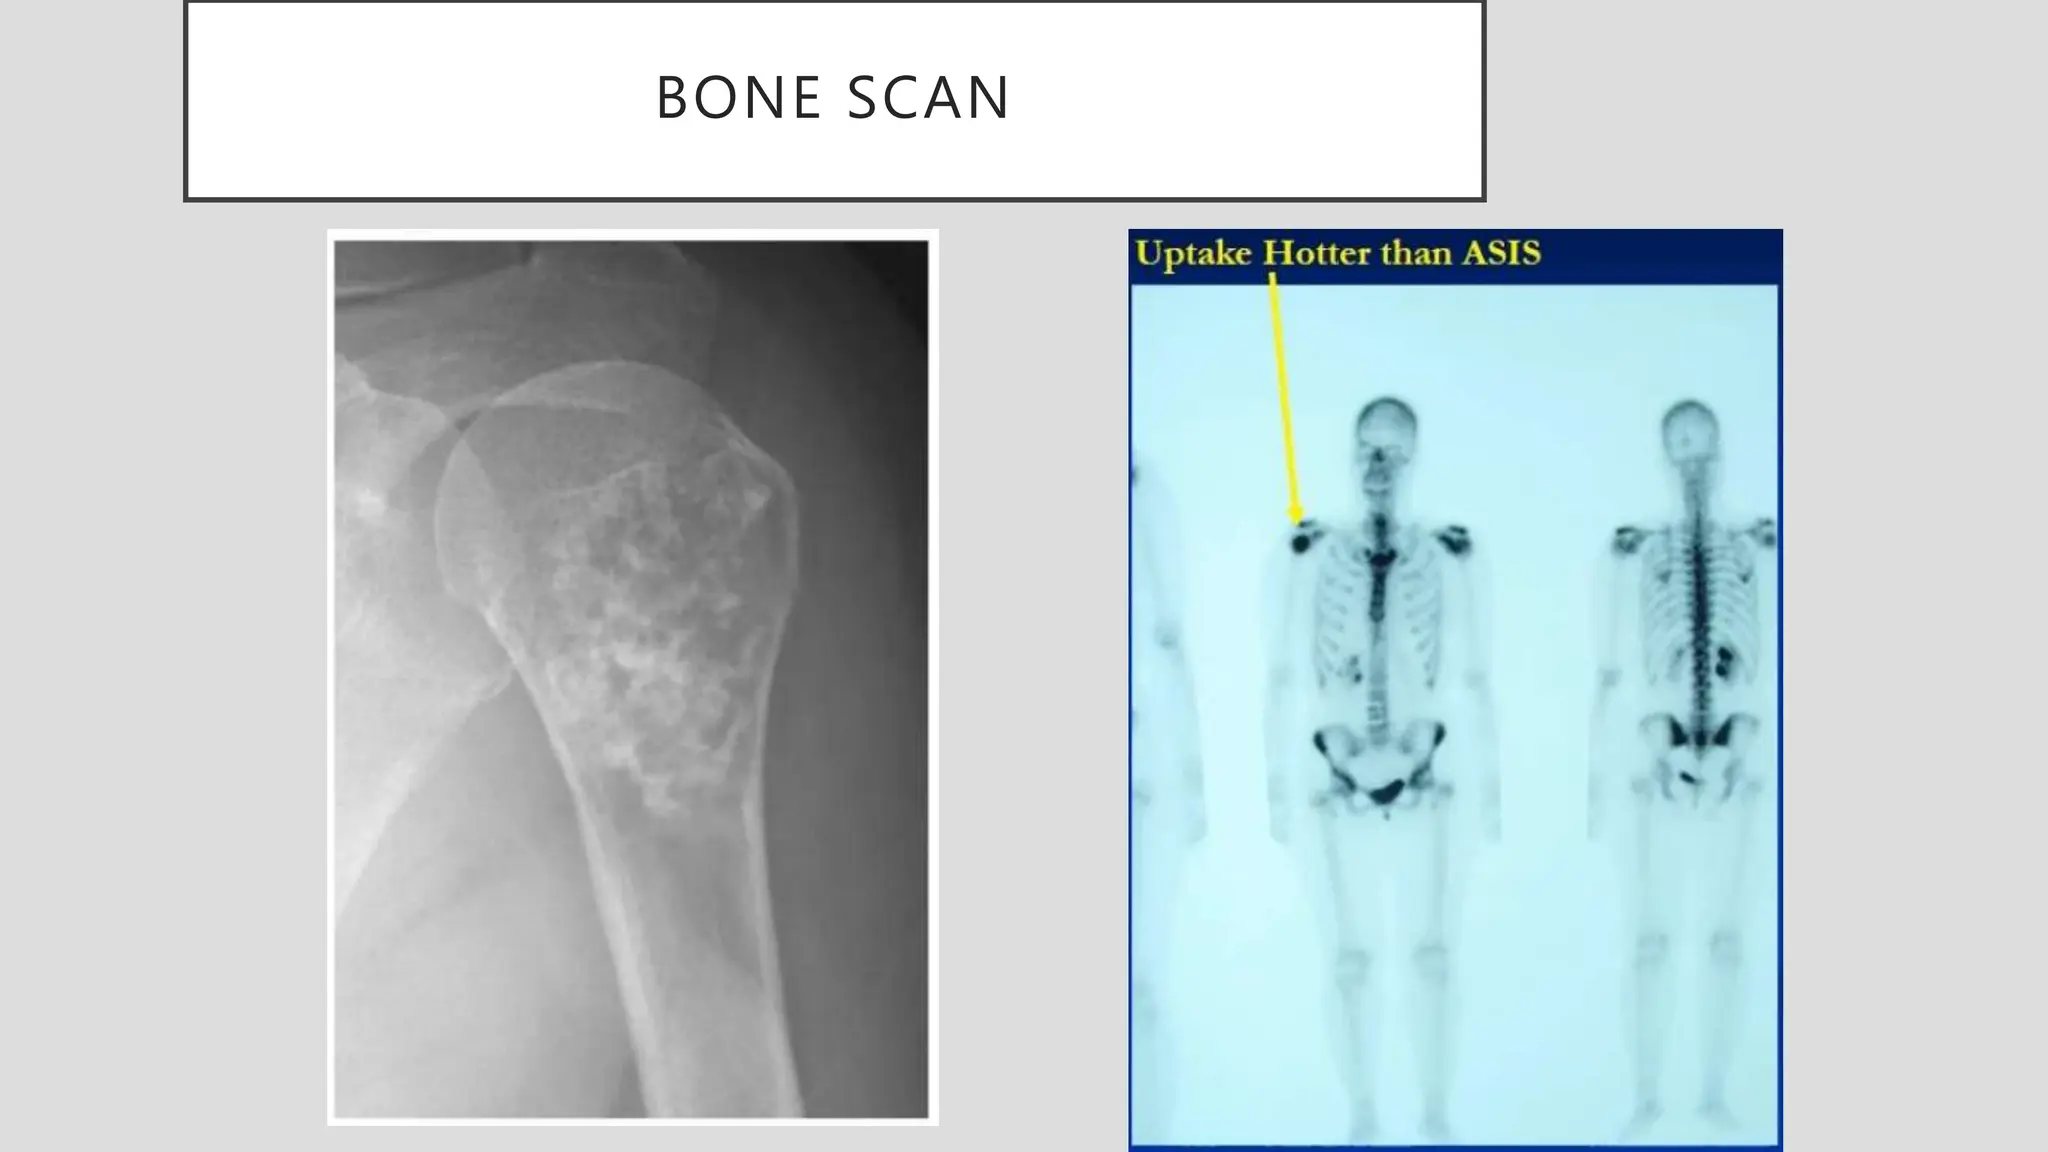

BONE SCAN

RADIOGRAPH OF GRADE 2

CHONDROSARCOMA

RADIOGRAPH OF GRADE2 CHONDROSARCOMA